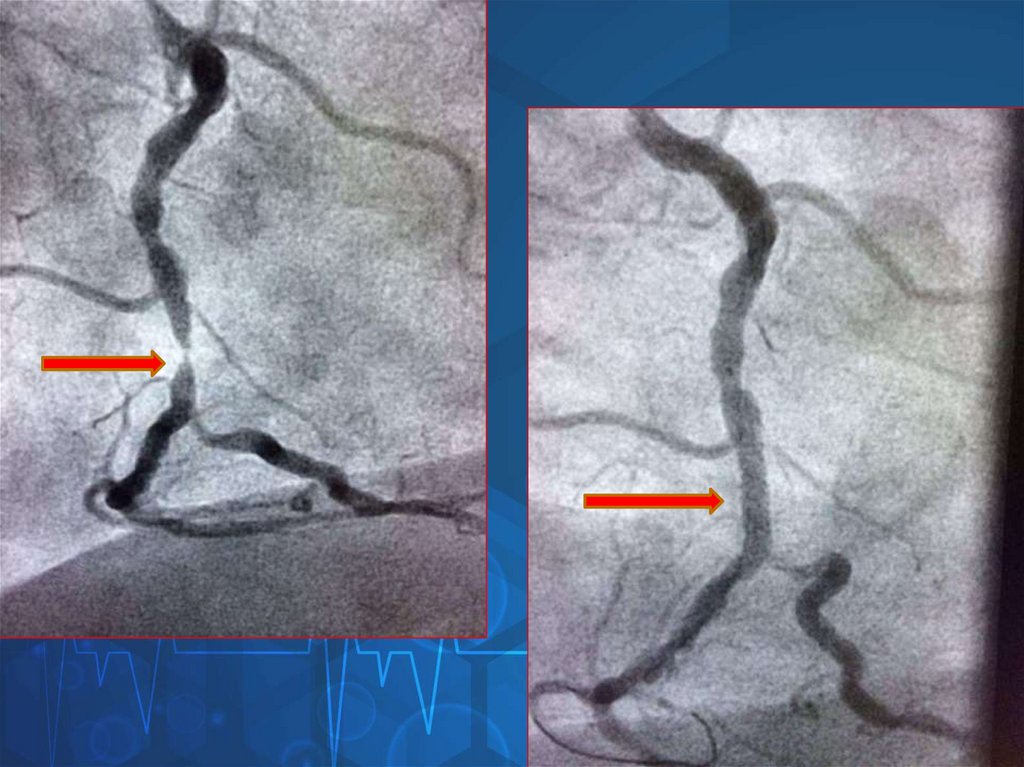

45. Ангиограмма до и после